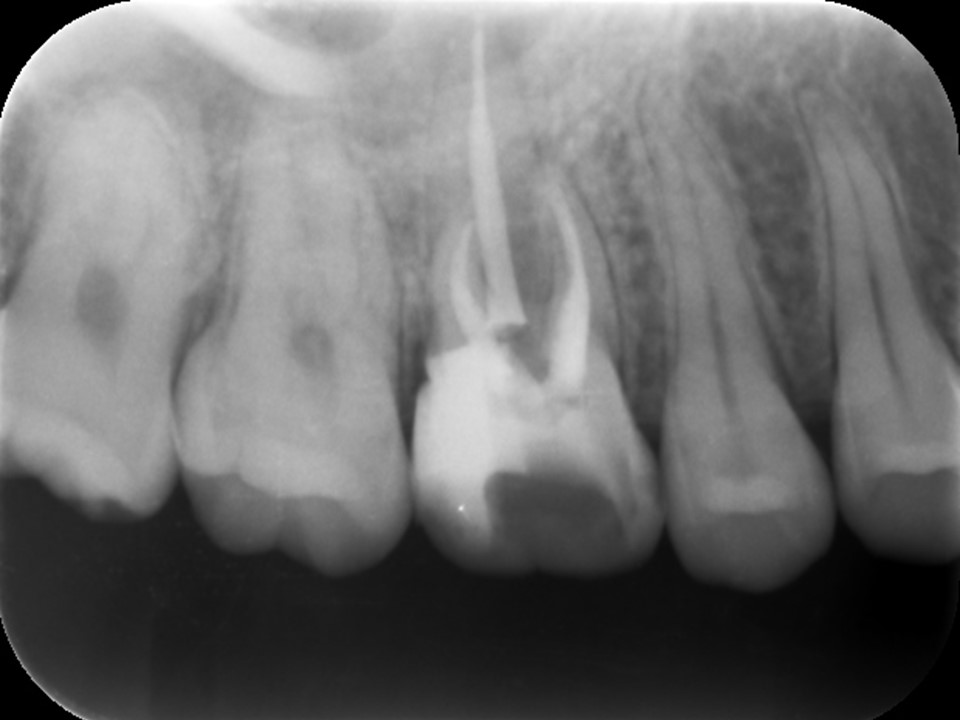

根管充填

症状が消失し、根管内に排膿や汚れが無くきれいになっていることを確認できたため、バイオセラミックシーラーとガッタパーチャにて根管充填を行いました(下写真)。

通常、症状や大きな根尖病巣、歯性上顎洞炎などが無ければこのまま歯冠修復処置を行いますが、このケースは炎症の広がりが大きいため3か月ほど経過観察を行うことにしました。

根管充填後のレントゲン画像です。根尖部までしっかりとお薬が詰まっているのが分かります。根尖病変および歯性上顎洞炎の予後を確認するため3か月ほど経過観察を行います。

予後確認・歯冠修復処置

根管充填3か月後のCT画像にて、根尖病変および歯性上顎洞炎の予後を確認しました。根尖病変は顕著に縮小して骨の再生が見られ、上顎洞炎はほぼ治癒していました(下写真)。

術前の症状もまったく無くなったので、ファイバーコアおよびオールセラミッククラウンにて歯冠修復処置を行いました。

根管治療14か月後のレントゲン及びCT画像では、根尖部のX線透過像および上顎洞内の不透過像は完全に消失しているのが分かります(下写真)。根尖部の骨の再生と上顎洞の正常化が認められ、根尖病変ならびに歯性上顎洞炎は完全に治癒しました。

根管充填3か月後のCT画像です。根尖病巣は顕著に縮小しており、骨の再生を認めます(赤矢印)。上顎洞の炎症も消退し、ほぼ正常像を呈していることが分かります(黄矢印)。病状が治癒傾向を認めるため、歯冠修復処置を行っていきます。

根管治療14か月後のレントゲンおよびCT画像です。術前にあった根尖部のX線透過像(赤矢印)ならびに上顎洞内のX線不透過性の亢進(黄矢印)は完全に消失し、根尖病変および歯性上顎洞炎は良好に治癒しているのが確認できます。